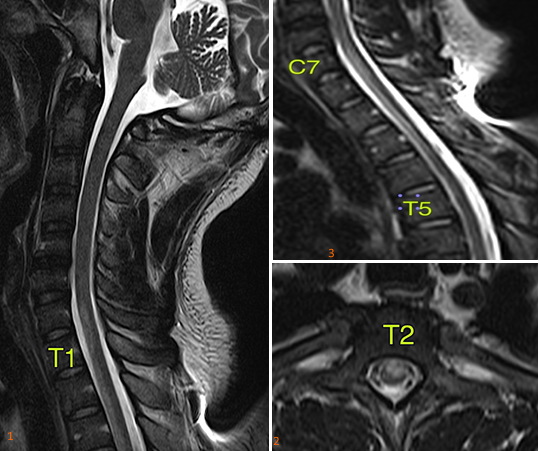

Spontaneous anterior spinal cord syndrome is uncommon and very rare in young adults. It affects the vascularization of the anterior 2/3 of the spinal cord, causing acute motor paralysis and sensory loss (pain and temperature) below the level of injury. Any vascular process that limits and interferes with the blood flow in the spinal cord region may be the etiologic cause. However, spontaneous,  thrombophilia causes in young adults have rarely been reported in the world literature. Antithrombin III (ATIII) is a blood protein that blocks the formation of abnormal blood clots and, at low levels predisposes to thrombus formation, favoring the occurrence of thromboembolic events in various organs. ATIII deficiency has remarkably higher risk rates for thromboembolic events, than those reported for other thrombophilia. In addition, thrombosis can occur early and recurrently. Thrombosis is a complex disease, and ATIII deficiency shows remarkably heterogeneous clinical range with vascular events from a young age and recurrently. The onset of the hematologic picture can vary greatly, as environmental as well as genetic factors interfere in the modulation of the biological and clinical phenotypes of thrombosis related to antithrombin deficiency (Figure 1).

Figure 1 Sagittal T2-weighted sequence of the spine with signal alteration in the anterior third of the spinal cord. 2. axial T2-weighted sequence observes signal alteration in the anterior third of the spinal cord with predominance of grey matter involvement. With predominance of involvement in the gray matter. 3. extension of the alteration in the anterior third of the spinal cord (C7-T5).

In this case, the patient presented with acute pulmonary involvement with acute pulmonary thromboembolism and anterior spinal artery occlusion as the first manifestation of the hematologic disease. Antithrombin III deficiency was detected and confirmed in blood tests, and elucidated as the primary etiologic cause, since there are no other commemoratives. The patient had no family history of hematologic disease and no history of previous thrombosis. The patient showed a good therapeutic response with gradual improvement of the motor part, after 30days of hospital discharge, the patient was able to ambulate on his own. He is on full anticoagulation on sodium warfarin 5mg (5x/week) and physical therapy for motor rehabilitation 3x/week. After 8months of the event, there was a complete motor recovery, being able to perform complex motor activities independently, such as driving and soccer practice; however, there was partial improvement in thermal and pain sensitivity, and a complaint of decreased sensitivity to sexual activities.1–4